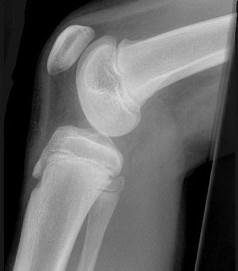

女,请根据其正常膝关节影像图像,判断其最可能的年龄 ( )A、23岁左右B、29岁左右C、11岁左右D、17岁左右E、5岁左右

问题 女,请根据其正常膝关节影像图像,判断其最可能的年龄 ( )

选项 A、23岁左右 B、29岁左右 C、11岁左右 D、17岁左右 E、5岁左右

答案 C